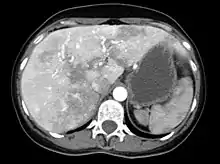

The symptoms produced by AVMs in the liver depend on the type of abnormal connection that they form between blood vessels. If the connection is between arteries and veins, a large amount of blood bypasses the body's organs, for which the heart compensates by increasing the cardiac output. Eventually congestive cardiac failure develops ("high-output cardiac failure"), with breathlessness and leg swelling among other problems.[1][6] If the AVM creates a connection between the portal vein and the blood vessels of the liver, the result may be portal hypertension (increased portal vein pressure), in which collateral blood vessels form in the esophagus (esophageal varices), which may bleed violently; furthermore, the increased pressure may give rise to fluid accumulation in the abdominal cavity (ascites). If the flow in the AVM is in the other direction, portal venous blood flows directly into the veins rather than running through the liver; this may lead to hepatic encephalopathy (confusion due to portal waste products irritating the brain). Rarely, the bile ducts are deprived of blood, leading to severe cholangitis (inflammation of the bile ducts).[1][6] Liver AVMs are detectable in over 70% of people with HHT, but only 10% experience problems as a result.[2]

Liver AVMs may be suspected because of abnormal liver function tests in the blood, because the symptoms of heart failure develop, or because of jaundice or other symptoms of liver dysfunction. The most reliable initial screening test is Doppler ultrasonography of the liver; this has a very high sensitivity for identifying vascular lesions in the liver. If necessary, contrast-enhanced CT may be used to further characterize AVMs.[1][2][6] It is extremely common to find incidental nodules on liver scans, most commonly due to focal nodular hyperplasia (FNH), as these are a hundredfold times more common in HHT compared to the general population. FNH is regarded as harmless. Generally, tumor markers and additional imaging modalities are used to differentiate between FNH and malignant tumors of the liver. Liver biopsy is discouraged in people with HHT as the risk of hemorrhage from liver AVMs may be significant.[6][7] Liver scans may be useful if someone is suspected of HHT, but does not meet the criteria (see below) unless liver lesions can be demonstrated.[7]

Given that liver AVMs generally cause high-output cardiac failure, the emphasis is on treating this with diuretics to reduce the circulating blood volume, restriction of salt and fluid intake, and antiarrhythmic agents in case of irregular heart beat. This may be sufficient in treating the symptoms of swelling and breathlessness. If this treatment is not effective or leads to side effects or complications, the only remaining option is liver transplantation. This is reserved for those with severe symptoms, as it carries a mortality of about 10%, but leads to good results if successful.[6][7] The exact point at which liver transplantion is to be offered is not yet completely established.[6] Embolization treatment has been attempted, but leads to severe complications in a proportion of patients and is discouraged.[5][6][7]